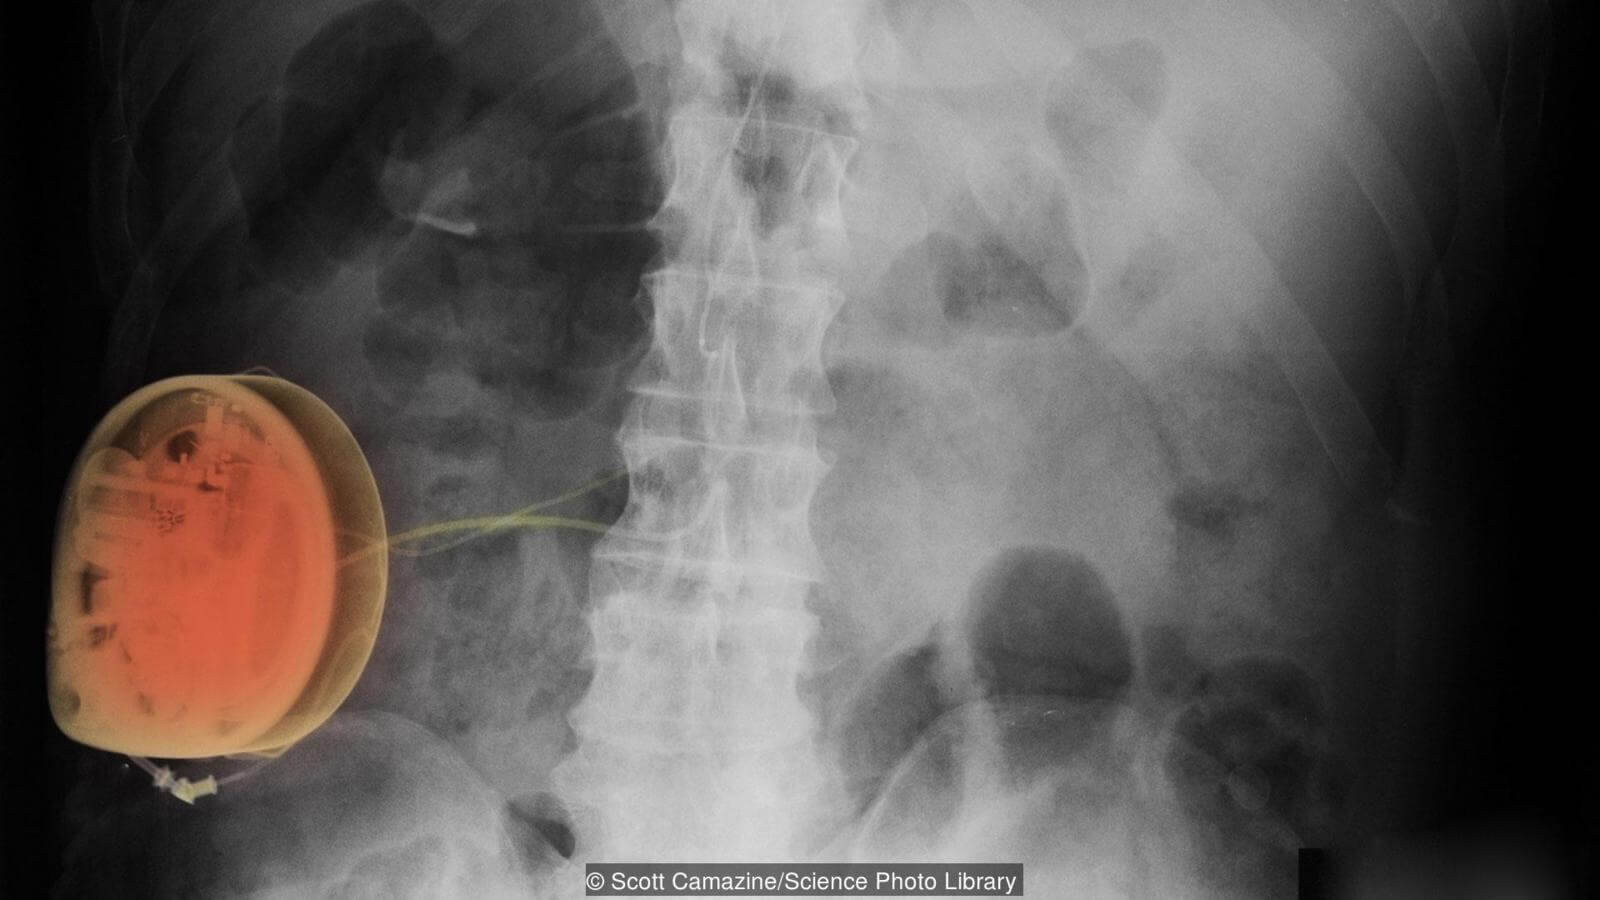

«Мы были первым центром в мире, который начал использовать стимуляцию спинного мозга», гордо говорит Аль-Каизи. «Мы пытаемся посылать небольшие электрические сигналы спинному мозгу, вставляя провод в эпидуральную область. Это всего один-два вольта, поэтому пациент чувствует только покалыванием над местом, в котором болит, но не реальную боль. Пациент не чувствует ничего, кроме того, как его боль утихает. Это не инвазивная процедура — мы отправляем пациентов домой в тот же день».